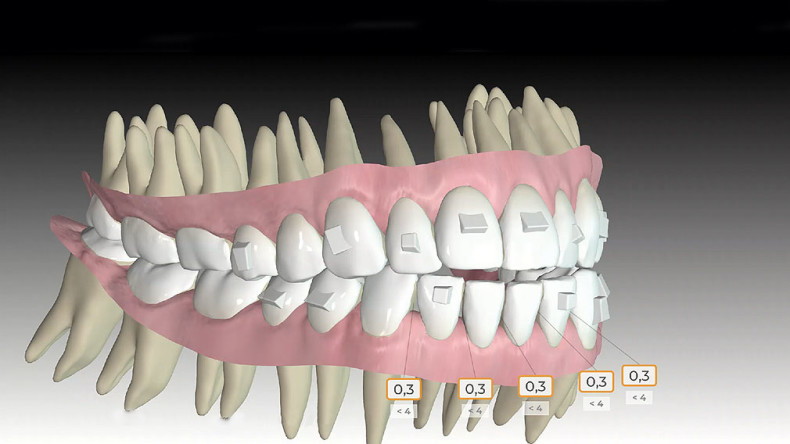

Dazu wurde die Approver 3D© Software eingesetzt, welche neben der Kronenbewegung auch die Bewegung der Wurzeln simulieren kann. Es wurden 20 Schienen und eine approximale Schmelzreduktion (ASR) an den unteren Frontzähnen zwischen 33 und 43 von je 0,3 mm geplant.

Durch sogenannte Optimized-Extrusion-Attachments wurde eine Extrusion der oberen Frontzähne von max. 2,3 mm und der unteren Frontzähne von max. 1,4 mm geplant (Abb. 4a–c). Mithilfe einer leichten Expansion der Prämolarenregion konnte der Platzmangel im Oberkiefer ohne ASR kompensiert werden.